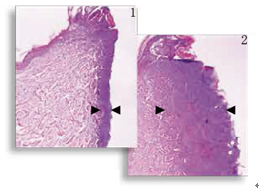

圖1,2

減輕熱損傷 組織學(xué)顯示,對比標(biāo)準(zhǔn)的電切尖端切口(圖2 ),表觀切口(圖1)明顯熱損傷減少